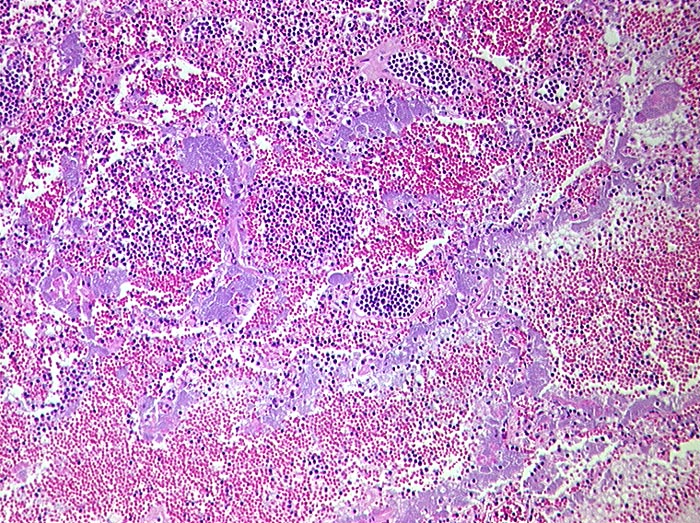

AP/ Areaktive Pneumonie

Areaktive Pneumonie

Entzündung infektiös

Lunge

Morphologie